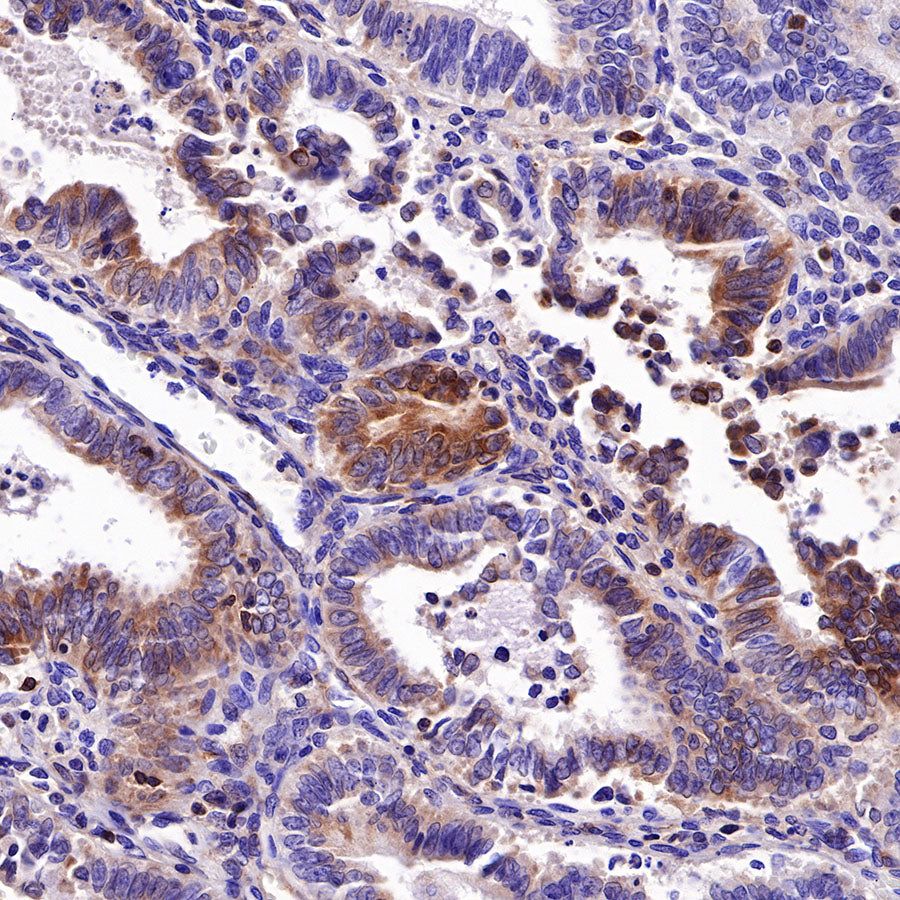

Picture

Picture

Immunohistochemistry